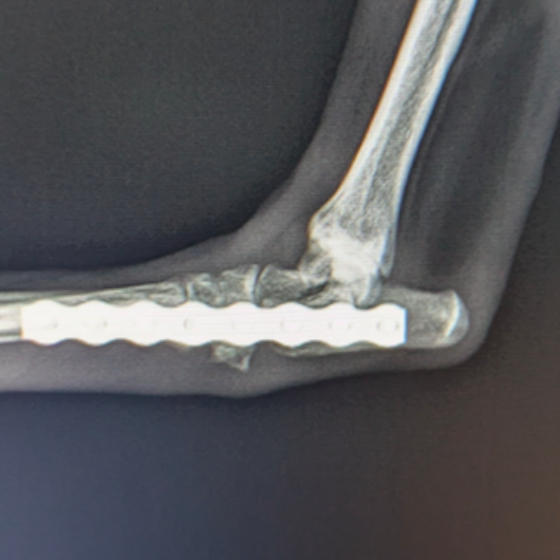

外科の前十字靱帯断裂のページに、小型犬のTPLO手術(脛骨高平部水平化骨切り術)を行った症例を追加致しました。大腿骨と脛骨を繋ぐ靱帯の一つである前十字靱帯は、断裂してしまうと膝の関節が不安定となり関節炎が進行し、またクッションの役割を果たしている半月板にもダメージが加わり痛みを生じて正常な歩行が出来なくなります。一度断裂してしまうと自然治癒は難しく、根本的な治療としては手術が必要となります。手術方法として、人工糸を靱帯の代用とする「ラテラルスーチャー法」や、脛骨の一部を切り角度を調整し膝関節を安定化させる「TPLO」などが挙げられますが、術後の回復の早さなどから近年では多くの場合後者が選択されています。当院ではFixinmicroプレートを使用して小型犬のTPLO手術を実施しております。